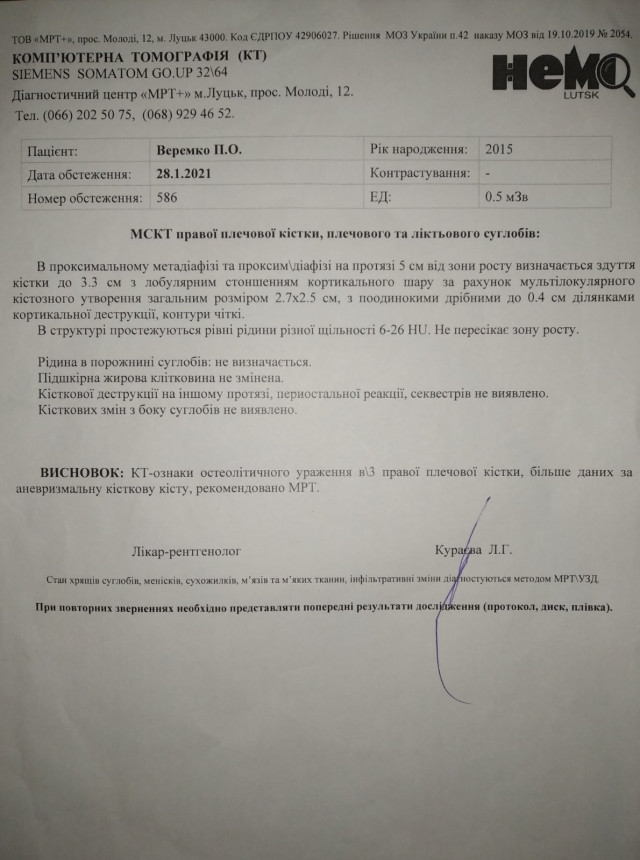

Шестирічному Павликові Веремку з прикордонного села Борового, що на Любомльщині (нині Ковельський район), встановили непростий діагноз – аневризмальна кісткова кіста правої плечової кістки, консолідований патологічний перелом правої плечової кістки. На хлопчика чекає складна операція із видалення частини ураженої кістки та довга реабілітація.

Обласні спеціалісти порекомендували спостерігатися й далі. А вже коли робили контрольні знімки, з’ясувалося, що пухлина почала збільшуватися. Дитині встановили інший діагноз – аневризмальна кісткова кіста.

Зараз ручка в дитини спухла й почала боліти. Пухлина збільшилася й тепер вона 2,5 на 2,7 см і має відростки по 4 мм.